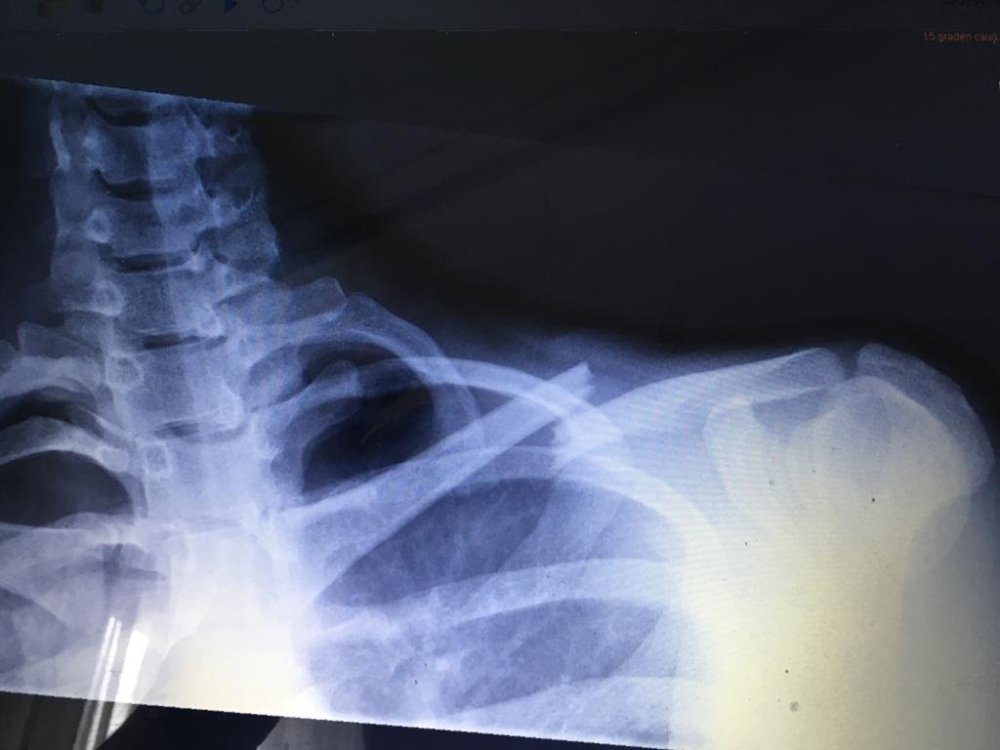

Wat heb ik eraan overgehouden? Een sleutelbeen breuk en een paar hele diepe schaafwonden.

Ik had me erg verheugd op het mooie schema dat eraan zat te komen, maar helaas moet er het een en het ander aangepast worden. Volgende week zou ik namelijk naar China vertrekken voor een aantal wedstrijden, maar dit gaat niet door. In plaats daarvan zal ik eerst een operatie moeten ondergaan en herstellen.